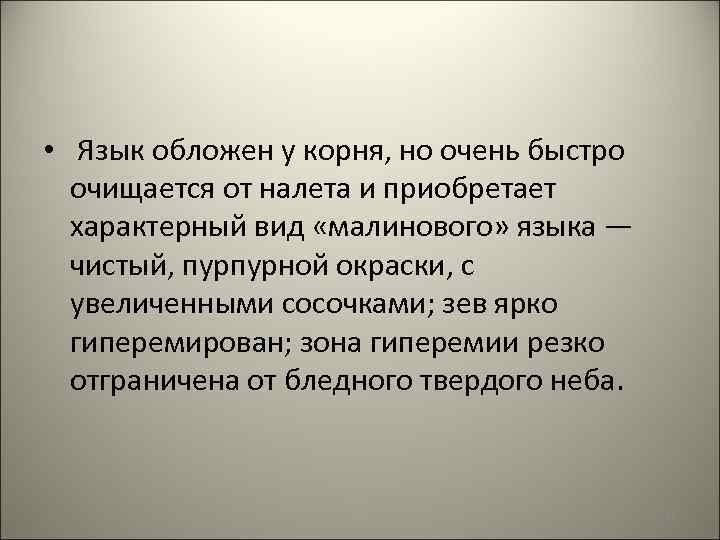

• Язык обложен у корня, но очень быстро очищается от налета и приобретает характерный вид «малинового» языка — чистый, пурпурной окраски, с увеличенными сосочками; зев ярко гиперемирован; зона гиперемии резко отграничена от бледного твердого неба. 148